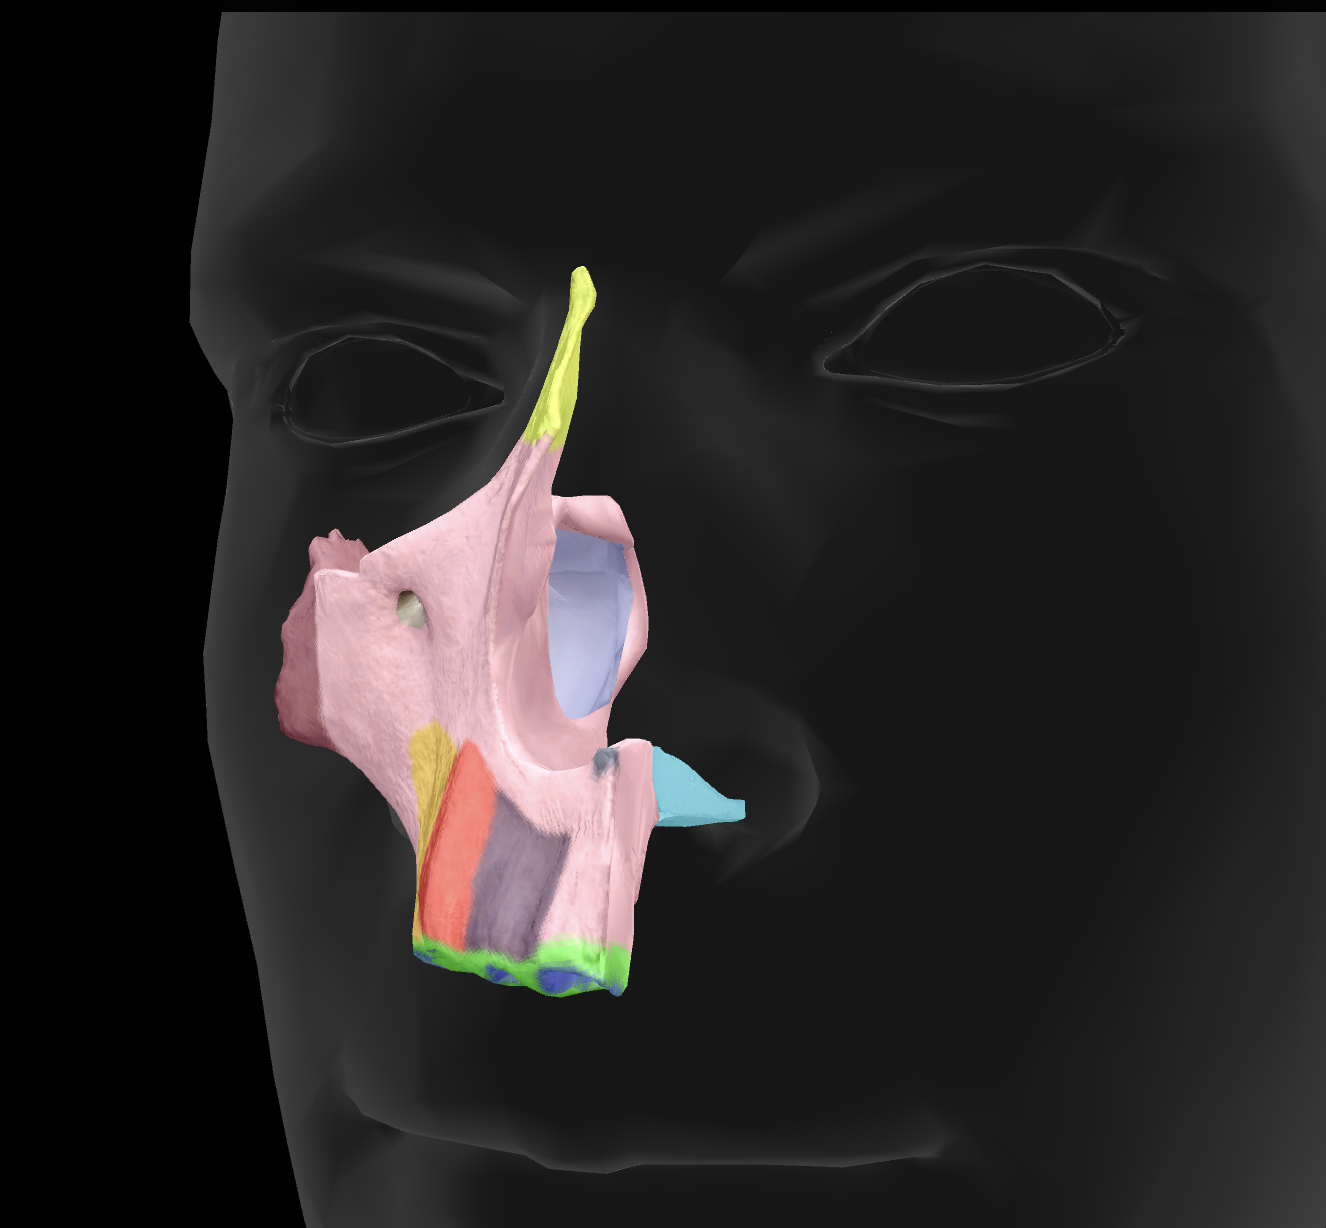

What features make up the nasal septum?

perpendicular plate of ethmoid bone and vomer

What is the name of this feature?

perpendicular plate

What is the name of this feature?

middle nasal conchae

What is the name of this feature?

superior nasal conchae

inferior orbital fissure